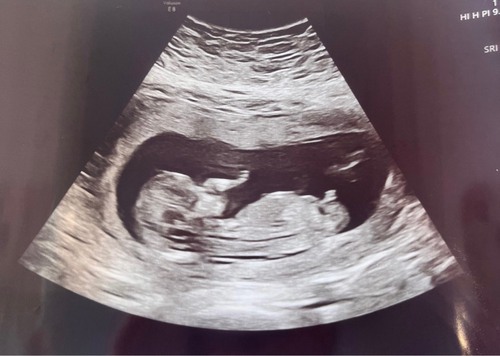

Deze is van vandaag precies met 13 weken 🥰 geen idee of er iets te zien is want ik heb geen verstand van de nub 😅

Ik vind dit niet echt een typische jongens nub maar ook geen meisjes nub hahaha! Woensdag geslachts echo. Wat vermoeden jullie?